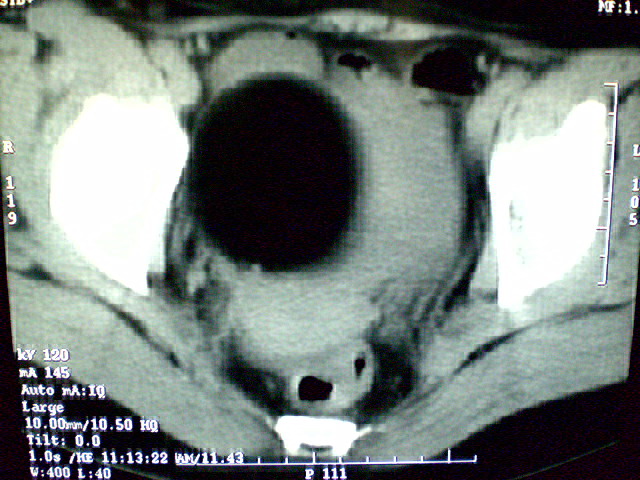

f 60y,b超提示脂肪瘤.[img][/img]

右侧附件囊性畸胎瘤,三种组织均见.

右侧附件囊性畸胎瘤.

那个高密度灶形状好象牙齿。典型,收藏了

脂肪密度肿块,内可见团块状影,典型皮样囊肿

的确比较典型的畸胎瘤!不过,应该确切的说是盆腔畸胎瘤,右侧附件来源的可能性比较大。

有钙化,畸胎瘤